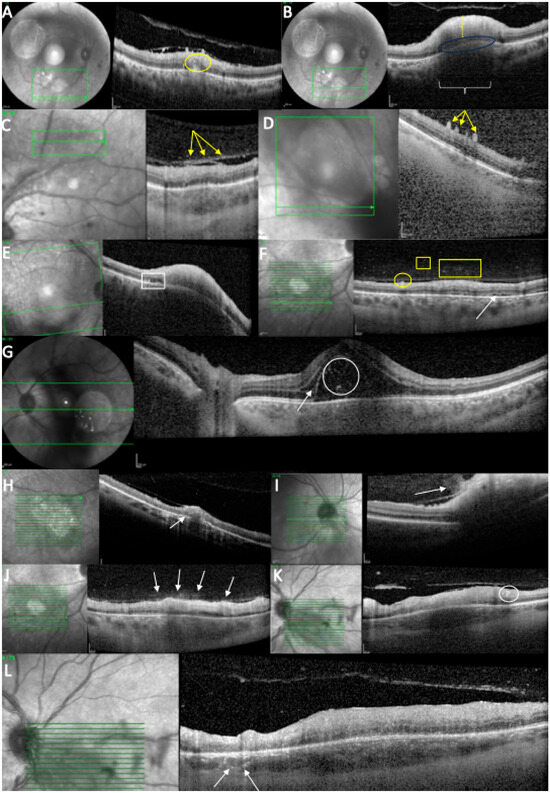

Structural Retinal Analysis in Toxoplasmic Retinochoroiditis: OCT Follow-Up with Three-Dimensional Reconstruction

Background: Ocular toxoplasmosis remains the leading cause of posterior uveitis worldwide. Optical coherence tomography (OCT) provides valuable insights into the structural alterations associated with this condition. The present study aimed to characterize the vitreous, retinal, and choroidal morphological changes observed during both [...] Read more.

Background: Ocular toxoplasmosis remains the leading cause of posterior uveitis worldwide. Optical coherence tomography (OCT) provides valuable insights into the structural alterations associated with this condition. The present study aimed to characterize the vitreous, retinal, and choroidal morphological changes observed during both the active and scarred stages of ocular toxoplasmosis using OCT imaging. A secondary objective was to evaluate the added value of three-dimensional reconstruction in the assessment of retinal lesions. Methods: A retrospective study was conducted on 12 eyes belonging to 12 patients diagnosed with toxoplasmosis retinochoroiditis (TRC). Optical coherence tomography (OCT) scans centered on the active lesions were qualitatively analyzed at baseline and follow-up. Additionally, a ResUNet model was trained to generate a full volumetric reconstruction of the retinochoroidal lesions in selected cases. Results: Twelve eyes were analyzed at a mean of 16.2 days from symptom onset. The mean follow-up duration was 144 days (range: 12–490 days). OCT imaging revealed characteristic alterations in the retina, choroid, and vitreous body, which were documented both at baseline and at follow-up. Representative cases were selected for three-dimensional reconstruction to illustrate the extent of retinal architectural involvement. Conclusions: OCT analysis refines our understanding of the structural damage associated with ocular toxoplasmosis, while three-dimensional reconstruction enhances our ability to visualize and interpret these alterations on a larger scale. Full article